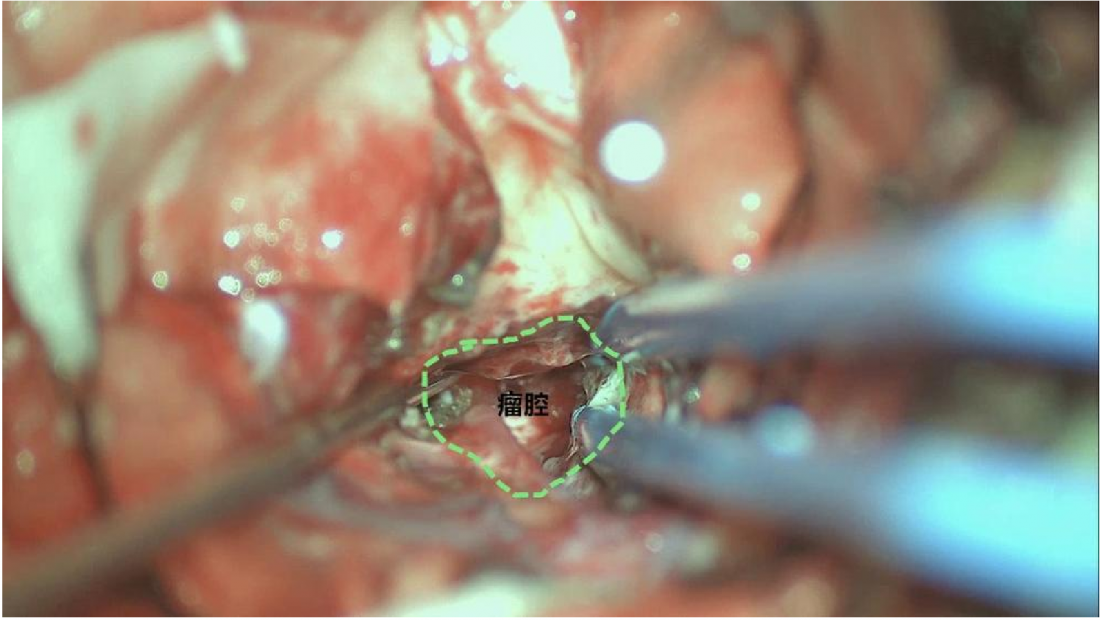

手术入路选择:考虑到患者肿瘤更靠近中线,因此为采取颞下入路及乙状窦后入路。我们采取经枕下正中入路,经第IV脑室切开桥脑,路径最近。因实质性血网手术切除的原则是整体剥除,否则出血汹涌。术中见肿瘤供血丰富,分离肿瘤,完整播出肿瘤。

2、血管网状细胞瘤分为实性及囊性,对于囊性血网的切除原则是切除瘤结节,而非将所有囊壁必须切除。实性血网需要将全部肿瘤部分切除,同时因其血运丰富,手术切除时应整体剥除,而不能分块切除。应该沿着肿瘤的边界仔细分离,因此在脑干内整体剥除肿瘤大大增加了手术的难度。手术时须严格沿肿瘤边界进行,减少对脑干的骚扰。主要最后将肿瘤的供血动脉全部断掉后,才能慢慢取出肿瘤。